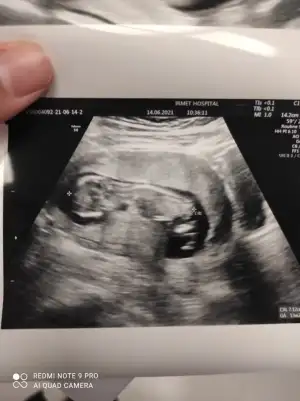

Erkek görünüyorSayfanıza da atmıştım??

Teşekkür ederimErkek görünüyor![]()

Erkek görünüyor

Çok teşekkürlerErkek görünüyor

Dr erkek diye tahmin etti ama elli kere de uyardıErkek görünüyor![]()